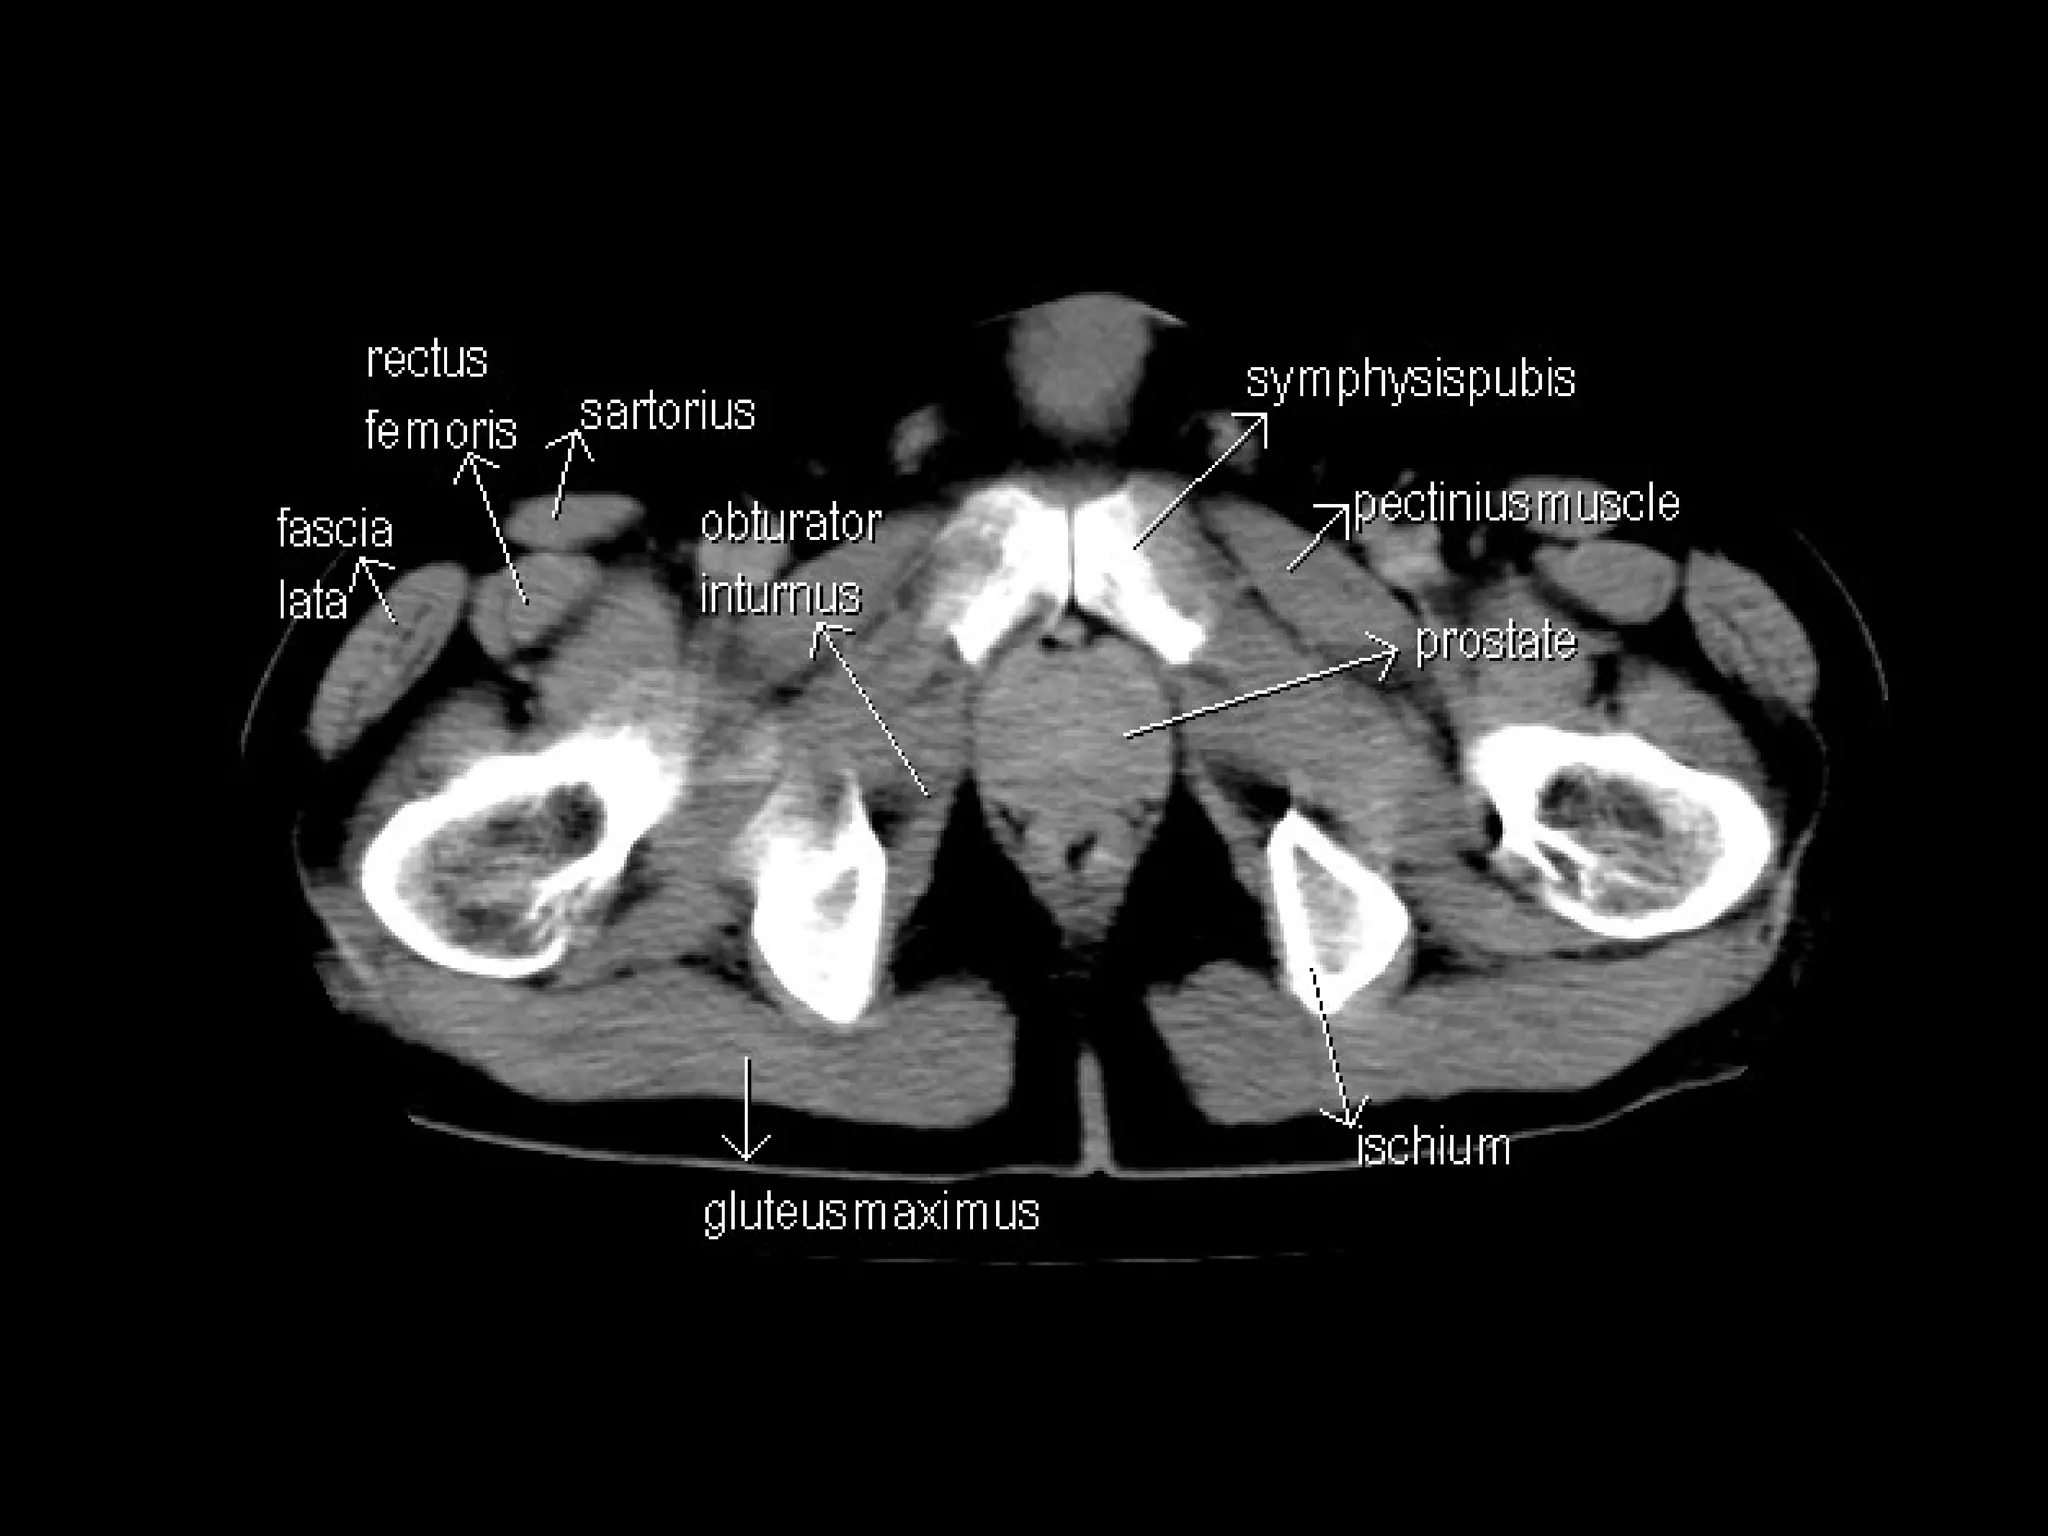

Radiographers are medical professionals who perform diagnostic imaging examinations and procedures to help physicians diagnose and treat diseases. They work under the supervision of radiologists to operate X-ray, CT, MRI, ultrasound and other medical imaging equipment and must have a strong understanding of human anatomy and pathology. Radiographers are responsible for correctly positioning patients, ensuring proper imaging techniques are used, and evaluating the quality of the resulting images.